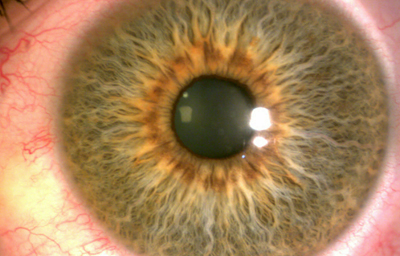

En la cara Anterior esta el pigmento que le da el color al Iris y dependiendo del grado de reabsorción u atrofia de esa capa anterior se pueden observar:

Las Criptas de Fuchs: que son pequeñas aberturas alrededor del collarete, producto de la atrofia o reabsorción de la hoja anterior del iris, que le permiten al estroma y a los tejidos mas profundos estar en contacto con el humor acuoso.

Cuando el Iris no tiene criptas, se considera que la reabsorción u atrofia de la hoja anterior (memb. pupilar) se detuvo en el circulo menor.